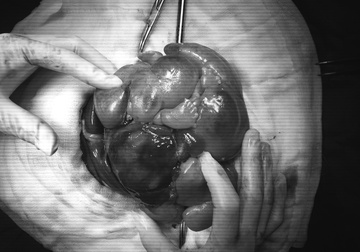

Bé gái sơ sinh mang khối u gần giống thai nhi trong bụng. Ảnh: Thúy Nguyễn.

Trong lúc phẫu thuật, các bác sĩ ghi nhận khối u có dạng bào thai. Túi chứa dịch nằm cạnh khối này tương tự túi ối, cùng với nhiều cấu trúc như xương vai, xương ống, xương cột sống không hoàn chỉnh, tuy nhiên, hình dạng các chi trưởng thành khá rõ.

Sau hơn một giờ phẫu thuật, các bác sĩ loại bỏ thành công khối u trong bụng bé sơ sinh. Tình trạng hô hấp của bé được cải thiện rõ rệt.